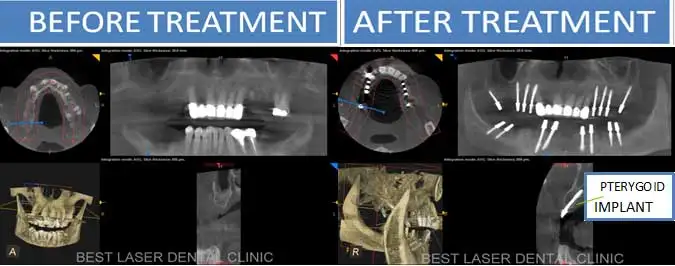

If you have been told by your dentist, that you have less bone or no bone in upper maxilla jaw, for dental implants, do not worry. These less bone situation can be successfully treated by pterygoid implants and fixed teeth can be given in 3-4 days.

Tubero pterygoid implants are indicated for patients who do not have enough bone for regular conventional implants. These implants are placed in the 2nd and 3rd molar region of the upper jaw.

– Avoids the need for sinus lift/bone grafts